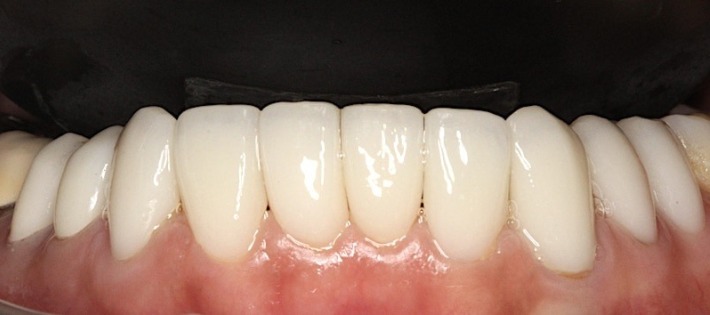

Pictured: A total of 10 all-ceramic crowns and ceramic veneers were quickly completed through digital dental technology.

Let’s take a look at the all-ceramic crown/ceramic veneer upgrade completed by Miss Deng in 2020. Is it more perfect?

Pictured: Photos of Miss Deng’s front teeth from various angles after completing the mandibular all-ceramic crown and ceramic veneer in 2020